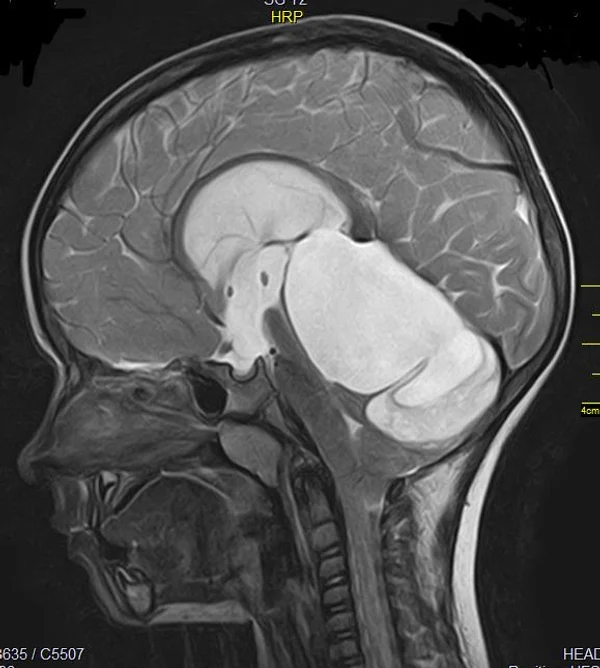

В качестве примера приведены 2 случая хирургического лечения новорожденных с врожденными опухолями головного мозга и позвоночного канала. У новорожденной девочки опухоль (хориодпапиллома) располагалась в области треугольника правого бокового желудочка (рис. 28 а, б). В возрасте 2-х недель жизни опухоль удалена. По данным МРТ головы с внутривенным введением контрастного препарата выполненной через 2 дня после операции опухоль удалена тотально (рис. 28 в). Послеоперационных осложнений не наблюдалось. У второго пациента 2-х нед. жизни врождённая опухоль (нейробластома) располагалась в позвоночном канале на уровне Th10-L3 позвонков (рис. 29 а) и распространялась в забрюшинное пространство. Клиническая картина заболевания складывалась из нижнего вялого парапареза и нарушения функции тазовых органов. Во время операции остистые отростки Th 11-L3 позвонков рассечены по средней линии. Дужки 6 данных позвонков надломлены и разведены в стороны. Опухоль располагалась экстрадурально, отделена от дорзальной поверхности дурального мешка и корешков спинно-мозговых нервов, после чего полностью удалена из позвоночного канала. Половинки дужек позвонков сведены к средней линии и сшиты между собой. Опухолевый узел в забрюшинном пространстве через 2 нед. удален онкологами. Через год после операции по данным МРТ рецидива опухоли нет (рис. 29 б). При спондилографии дефектов задней стенки и деформаций позвоночника не выявлено (рис. 29 в). Мальчик ходит, мочу и кал удерживает.